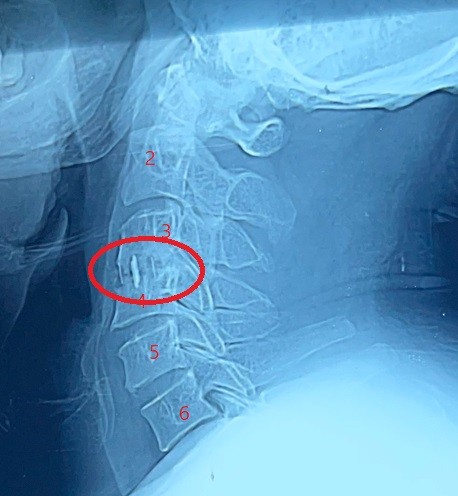

Fixation and dilatation of the cervical nerve canal to correct unsuccessful anterior cervical discectomy